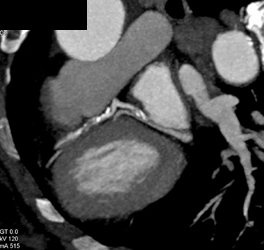

Coarctation of the Aorta With Dilated Ascending Aorta and Bicuspid Valve